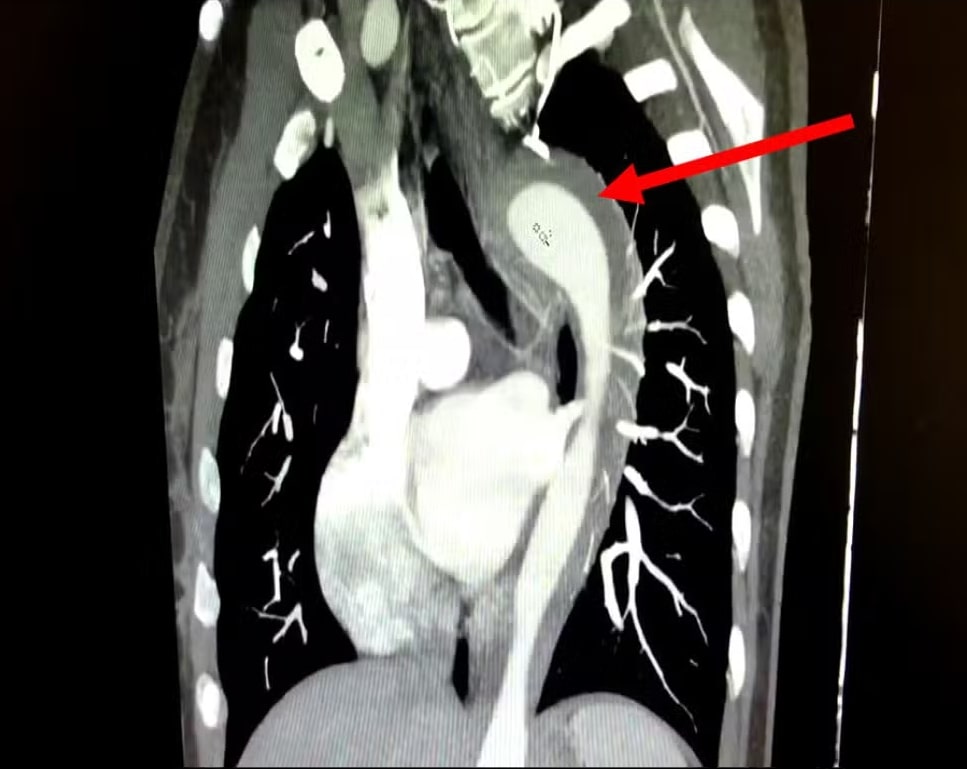

A mulher foi medicada e passou por exames que indicaram um hematoma intramural na aorta.

O hematoma intramural na aorta é uma condição grave que envolve o sangramento na parede da aorta. O quadro é considerado uma Síndrome Aórtica Aguda (SAA) e, se não tratado adequadamente, pode evoluir para aneurisma ou ruptura aórtica total, com risco de vida ao paciente.